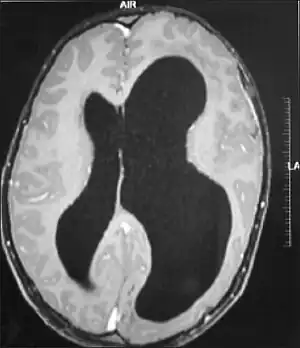

Hemimegalencephaly (HME), or unilateral megalencephaly, is a rare congenital disorder affecting all or a part of a cerebral hemisphere.[2] It causes severe seizures, which are often frequent and hard to control. A minority might have seizure control with medicines, but most will need removal or disconnection of the affected hemisphere as the best chance. Uncontrolled, they often cause progressive intellectual disability and brain damage and stop development.[3]

It should be suspected in infants or children with intractable, frequent seizures.[4] On a CT scan, the affected part is distorted and enlarged.[9] It can be diagnosed prenatally, but a lot of cases go undiagnosed until seizures begin. Ultrasound can display asymmetrical brain hemispheres.[5]